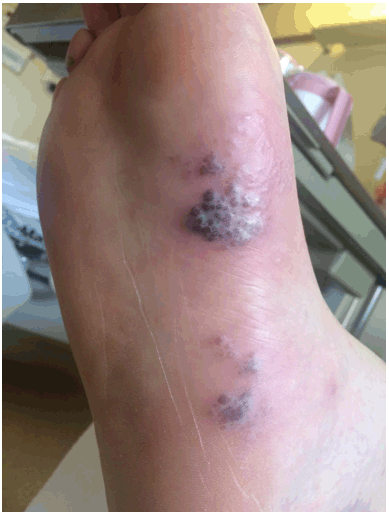

Upon admission, laboratory findings showed: blood pressure 125/74 mmHg and pulse 91 bpm 1 Resp:18 breaths/min, SaO2 98% on room air, temperature 36.4C, white blood cell count 3×109/L, platelet 122×103/µL, absolute neutrophil count 1.5, CD4 count 65 cells/mm3, viral load 1639 copies/mL. On physical examination, the rash was composed of small vesicles with surrounding erythema, and was painful to the touch. It was located mainly on the forehead (Figure 1), between the patient's toes (Figure 2) and plantar aspect of the foot (Figure 3), with scattered lesions on his legs, back (Figure 4), and abdomen (Figure 5). The vesicular lesions appeared to be in varying stages with no umbilication. The patient was immediately started on intravenous acyclovir 10 mg/kg IV q8hr [3], placed in isolation, and was monitored for progression of the lesions into the mouth or eyes. Within 24–36 hours, half of the body lesions had begun to crust over with no newly forming lesions. After 48 hours of treatment, all of the lesions crusted without further vesicle progression.

Figure 3: Hemorrhagic vesicles on right foot.